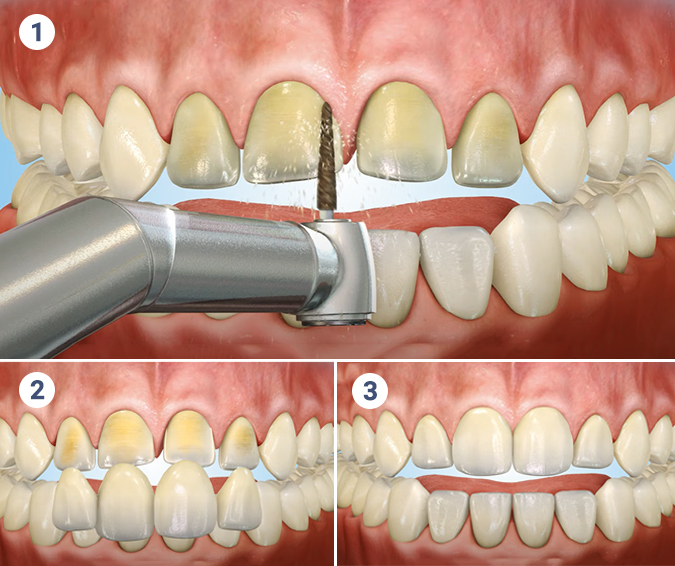

Ultrasonic scaling is a modern, pain-free method of deep cleaning your teeth. It uses high-frequency vibrations and water spray to remove plaque, tartar, and surface stains that regular brushing can’t eliminate.

This procedure not only enhances the brightness of your smile but also helps in preventing gum disease, bad breath, and other oral infections. It’s a crucial step in maintaining long-term dental hygiene and gum health.

Porcelain veneers are thin, custom-made shells that are bonded to the front surface of your teeth to enhance their appearance. They are ideal for correcting chipped, stained, misaligned, or uneven teeth.

Our veneers are crafted from high-quality porcelain that mimics the natural translucency of teeth, ensuring a beautiful and long-lasting smile. With minimal tooth reduction, you get maximum cosmetic improvement.